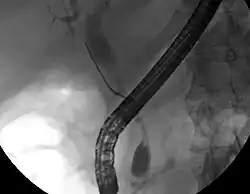

While abdominal imaging can be useful in the diagnosis of cholangiocarcinoma, direct imaging of the bile ducts is often necessary. Endoscopic retrograde cholangiopancreatography (ERCP), an endoscopic procedure performed by a gastroenterologist or specially trained surgeon, has been widely used for this purpose. Although ERCP is an invasive procedure with attendant risks, its advantages include the ability to obtain biopsies and to place stents or perform other interventions to relieve biliary obstruction.[12] Endoscopic ultrasound can also be performed at the time of ERCP and may increase the accuracy of the biopsy and yield information on lymph node invasion and operability.[56] As an alternative to ERCP, percutaneous transhepatic cholangiography (PTC) may be utilized. Magnetic resonance cholangiopancreatography (MRCP) is a non-invasive alternative to ERCP.[57][58][59] Some authors have suggested that MRCP should supplant ERCP in the diagnosis of biliary cancers, as it may more accurately define the tumor and avoids the risks of ERCP.[60][61][62]